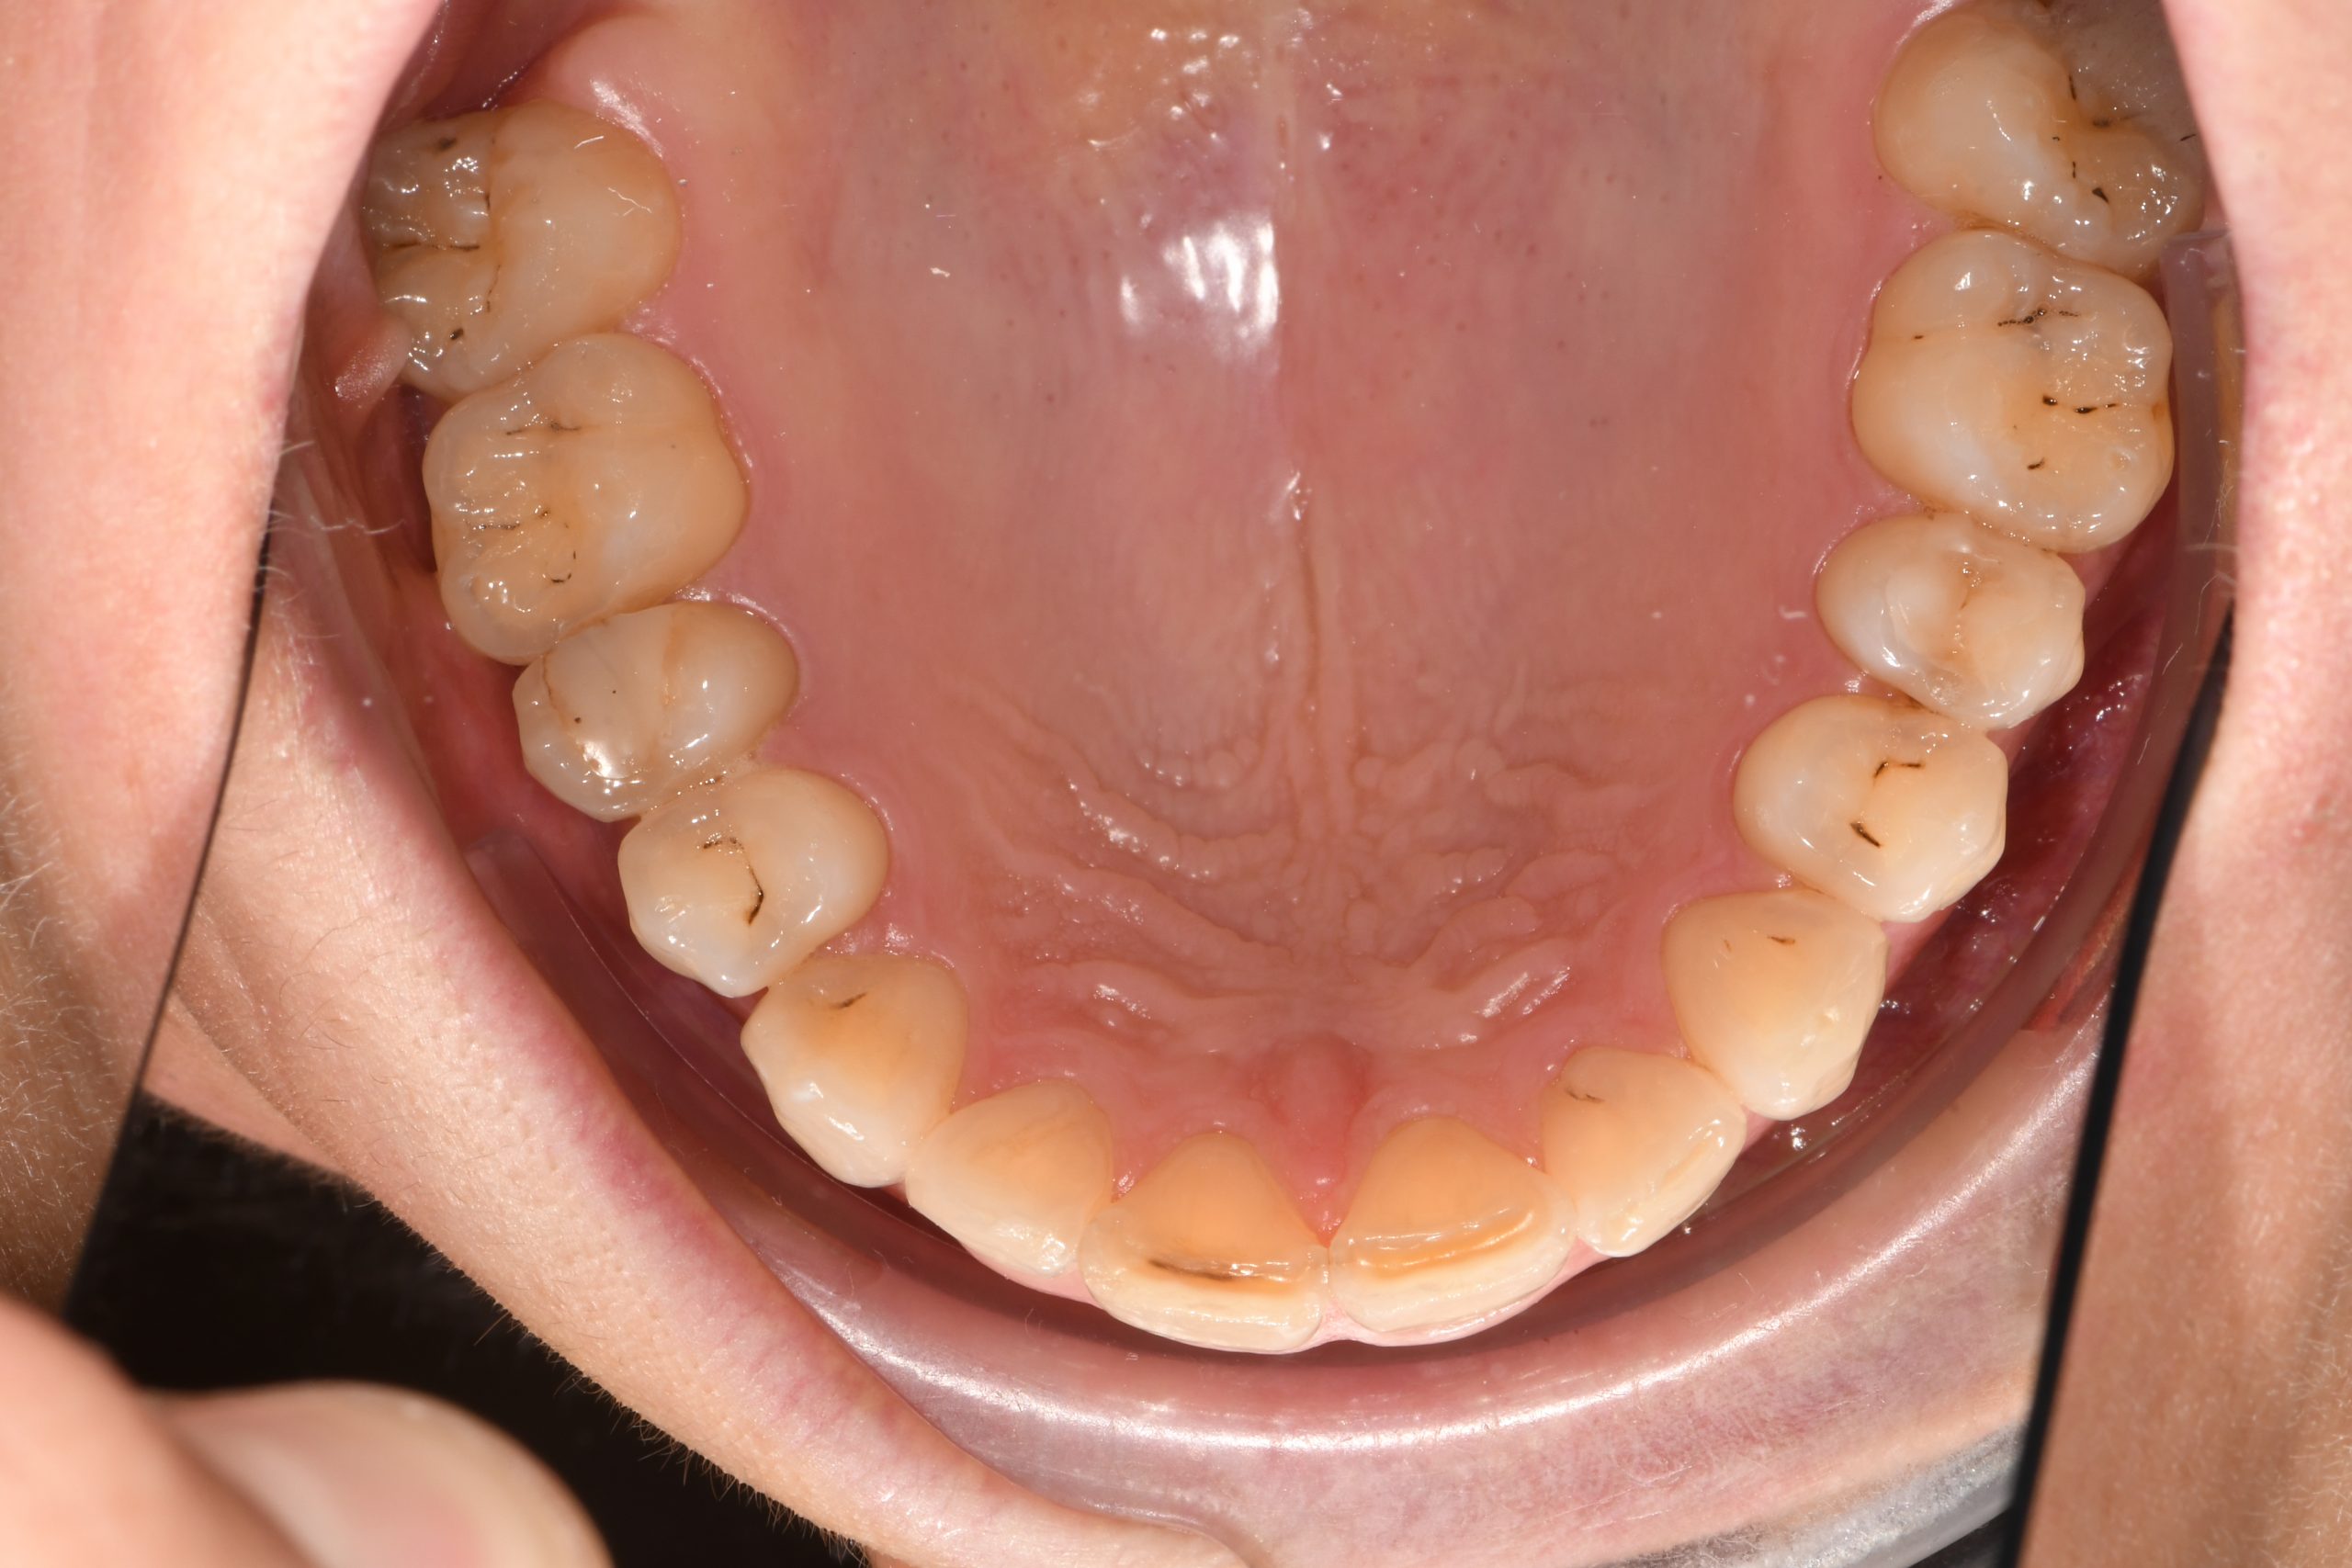

Az elmúlt évekből rengeteg szakmai referenciát tudnánk bemutatni, amelyek különböző fogszabályozási problémákat oldottak meg. Válogatva a több száz esetből, ezen az oldalon olyan képeket, információkat igyekeztünk bemutatni, amelyeknek a segítségével a jövőbeni pácienseinknek azt tudjuk üzenni: A Te fogsorod is lehet gyönyörű!

(Képeket a Pácienseink külön írásos beleegyezésével mutatjuk be!)